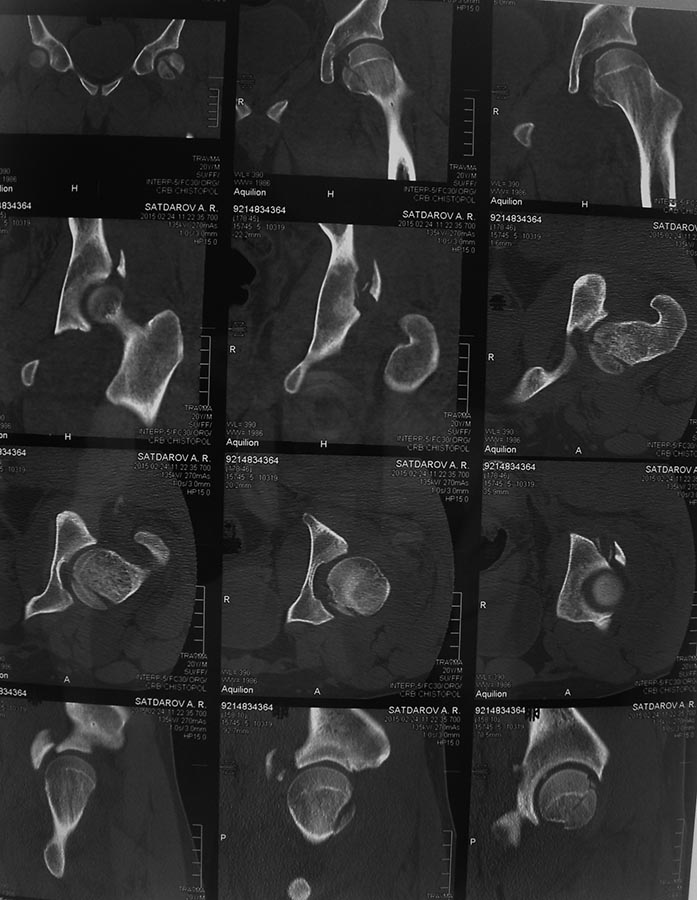

Молодой человек 20 лет ДТП 23.02.2015, Диагноз: Сочетанная травма.

Закрытый переломо-вывих головки и перелом заднего края вертлужной

впадины (Pipkin4) правой бедренной кости. Открытый подтаранный вывих

правой стопы. При поступлении в ЦРБ вправление вывиха головки бедра и

подтаранного вывиха стопы. Далее перевод к нам в Травмоцентр и

03.03.2015. через 8 дней операция, выполнен остеосинтез головки 3-мя

самокомпрессирующими винтами Autofix под разными углами с погружением в

субхондральный слой. Доступ Kocher-Langenbeck с флип-остеотомией

большого вертела и задним хирургическим вывихом головки бедра. В полости

сустава два свободно-лежачих фрагмента хряща головки, которые были

удалены. На снимках виден дефект хряща головки после репозиции.

Небольшой фрагмент заднего края фиксирован двумя спонгиозными винтами.